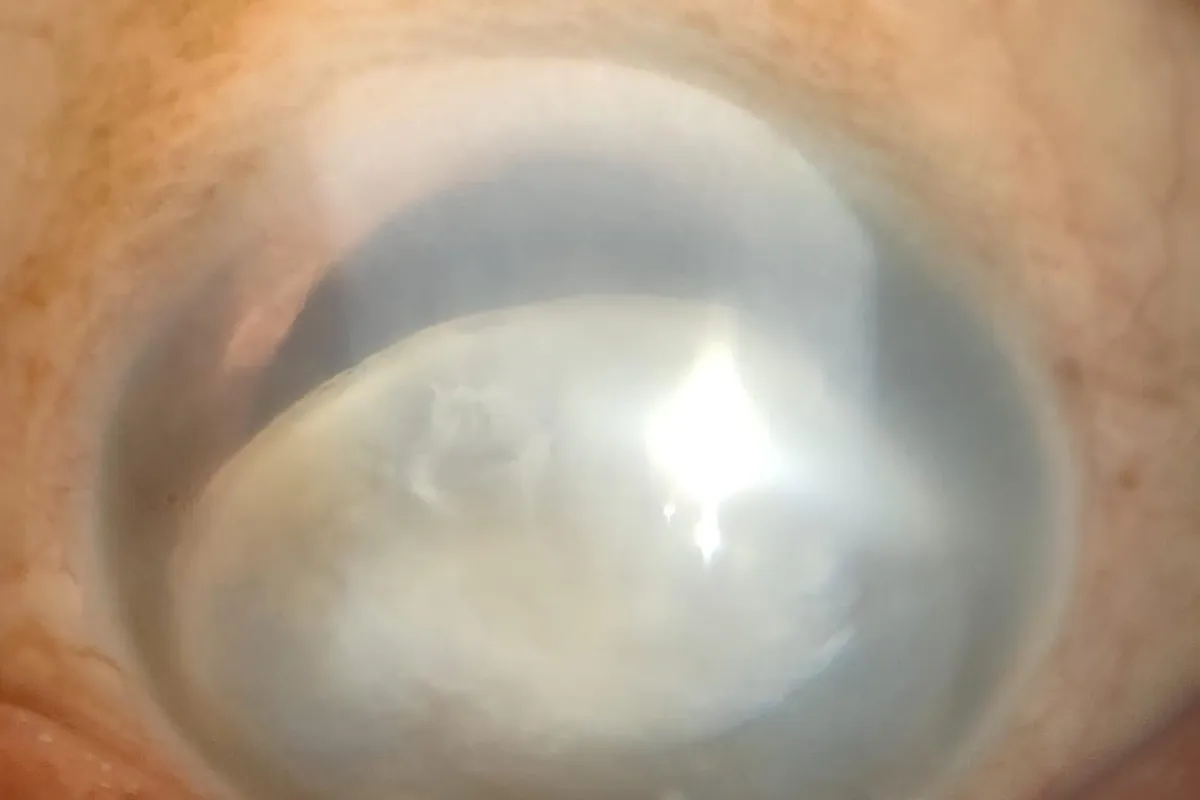

We handle complex cataract cases including mature cataracts, post-traumatic cataracts, subluxated lenses, and cataracts with associated ocular conditions. Our approach ensures optimal outcomes with enhanced visual recovery.